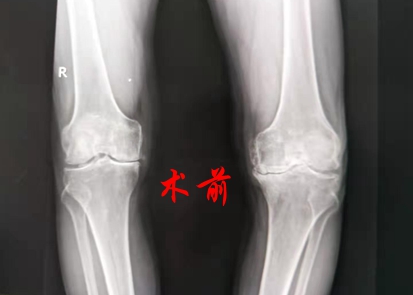

入院后,关节科负责人王开颜发现黄大伯的左膝关节严重变形,膝关节内翻屈曲挛缩畸形,无法伸直,屈曲在95度,并且内翻畸形达30度,行走困难,黄大伯被诊断为左膝关节骨性关节炎,他主动要求手术治疗解除痛苦。

术前,关节科团队为黄大伯详细做了检查。因黄大伯同时伴有心脏病、胃病、酒精肝,为保证手术顺利进行,关节科邀请综合内科、手术室、麻醉科等科室联合会诊,进行术前综合评估,并制订了详细的手术和术后恢复方案。3天后,刘卓华院长带领关节科专业团队为黄大伯实施了左侧人工膝关节置换术。该患者由于病程长、关节磨损严重,内侧平台骨缺损严重,因此手术最大的难点是要求操作精细,历经1个半小时,手术顺利完成。术后黄老伯生命体征平稳,第二天在专业康复师的指导下借助助行器行走。